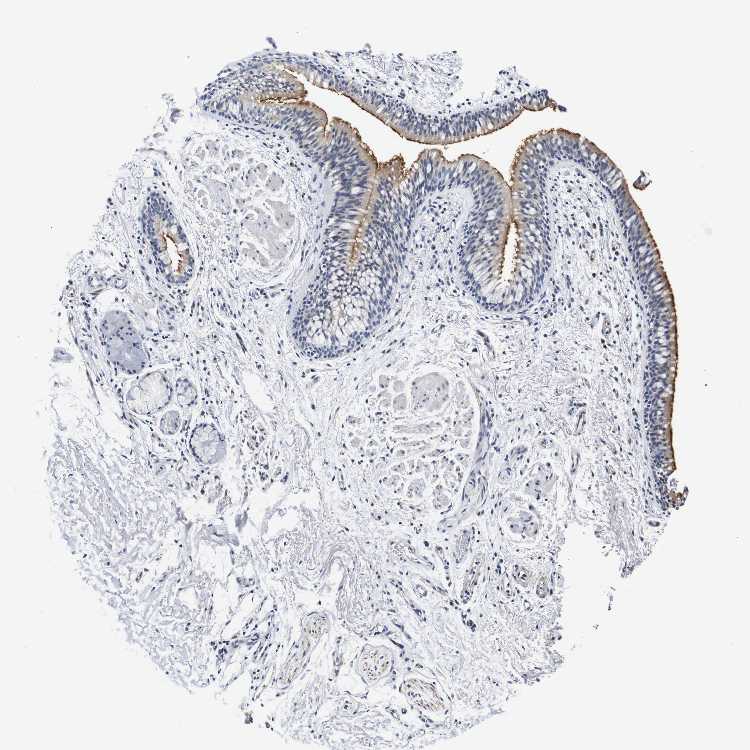

SOFT TISSUE 1 - Antibody stainingi

Antibody staining in the annotated cell types in the current human tissue is reported as not detected, low, medium, or high, based on conventional immunohistochemistry profiling in selected tissues. This score is based on the combination of the staining intensity and fraction of stained cells.

Each image is clickable and will lead to virtual microscopy that enables deeper exploration of all samples and also displays staining intensity scores, fraction scores and subcellular localization as well as patient and tissue information for each sample.

Antibody HPA013316Antibody CAB002496

Fibroblasts Not detectedNot detected

Peripheral nerve MediumNot detected